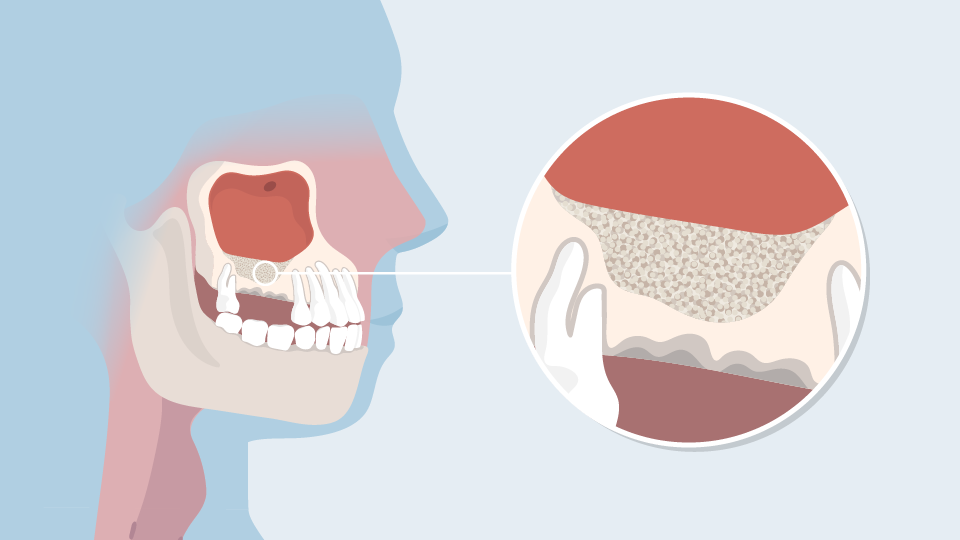

In deze Divi krijgt de patiënt uitleg over een sinusliftoperatie. De patiënt leert waarom er te weinig bot in de bovenkaak is voor een implantaat en hoe dit komt. Ook wordt uitgelegd hoe de operatie verloopt en wat de patiënt kan verwachten voor, tijdens en na de ingreep.

De patiënt wordt geïnformeerd door middel van animatie, illustratie en tekst.